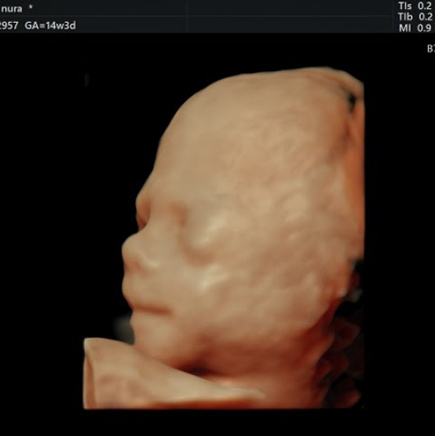

סקירה מערכות מוקדמת

בסקירת מערכות מוקדמת (שנקראת גם “סקירה ראשונה”) נסקרים רוב האיברים של העובר במטרה לאתר מומים וממצאים לא תקינים בשלב מוקדם של ההיריון

את הסקירה המוקדמת מומלץ לעשות בשבועות 14 עד 17 להריון